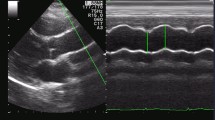

Calculation of Pulse Wave Velocity and Total Arterial Compliance

Aortic pulse wave velocity (aPWV) was estimated by determining the transit time via pulse wave analysis, similarly to the in vivo methodologies for aPWV measurement.12 The transit time between proximal and distal pressure waveforms was determined with an automated technique that located the minimum diastolic pressure in the waveform.5 The waveforms were recorded at arterial sites that resemble aPWV measurement in clinical practice; namely, the carotid and femoral artery (carotid-to-femoral PWV), as previously described,12,34 and shown schematically in Fig. 1 (Sites A and B, respectively). The “real” C T for each of the 1000 simulated cases, was directly calculated as the summation of volumetric compliance for all the arterial segments (at mean pressure), including the compliance of the terminal sites (Windkessel models). The resulting values of total compliance ranged between 0.126 and 2.256 mL/mmHg. Peripheral resistance had a minimum of 0.600 mmHg s/mL and a maximum of 1.681 mmHg s/mL. The computed C T and aPWV values were fitted according to the nonlinear power relationship given by Eq. (5). The following fit quality parameters were calculated: sum of square errors (SSE) R 2, and root mean square error (RMSE).